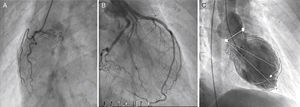

Case reportA 56-year-old Caucasian patient with COPD (irregularly treated with tiotropium bromide, acetylcysteine and mometasone) was admitted to the emergency room (ER) of our hospital with dyspnea and cough with sputum for two weeks. On admission to the ER, the patient was hemodynamically stable (systolic/diastolic blood pressure: 126/65 mmHg; heart rate: 98 bpm), eupneic at rest and with fever (39.1°C). Pulmonary auscultation revealed rumbles in the left hemithorax. The chest radiograph showed left paratracheal consolidation. There was no evidence of respiratory failure on arterial blood gas analysis. Laboratory tests revealed elevated leukocytes. After treatment with inhaled ipratropium bromide, the patient suffered severe bronchospasm and retrosternal chest pain accompanied by sweating and pallor. An electrocardiogram (Figure 1A), with pain, showed sinus tachycardia (heart rate 110 bpm), incomplete right bundle branch block, 2-mm ST-segment elevation in leads V1–V3 and Q waves in leads V3–V6. Given the possibility of an acute coronary syndrome, emergency coronary angiography was carried out, which showed normal coronary arteries (Figure 2A and B), severe systolic dysfunction with mid-apical akinesia and basal hypercontraction (Figure 2C). The echocardiogram confirmed severe compromise of left ventricular systolic function (LVSF), with akinesia of the mid-apical segments and an aneurysm-like dilatation (Figure 3). During hospitalization the patient remained hemodynamically and electrically stable, but the electrocardiographic pattern evolved with T-wave inversion in the left anterior precordial leads (Figure 1B) and plasma troponin I was elevated (peak value 2.28 ng/ml). After further use of ipratropium bromide, on the second day of hospitalization, the patient developed a new episode of marked bronchospasm and respiratory acidosis (pH 7.29; pCO2 53 mmol/l). He was started on non-invasive ventilation and was treated with hydrocortisone, inhaled salbutamol and furosemide, with progressive clinical improvement. He was also started on antibiotics (azithromycin plus ceftriaxone), but microbiological screening (bacteriological study of sputum and search for urinary antigens of Streptococcus pneumoniae and Legionella pneumophila) was negative. There was no significant increase in C-reactive protein levels. Repeat chest radiograph documented pulmonary overinflation. To assess the severity of lung disease, respiratory function tests were performed, which revealed a severe obstructive ventilatory syndrome with lung hyperinflation. The patient underwent a chest computed tomography scan on the fifth day after admission that showed scattered bronchiectasis and a ground-glass pattern in the area of the left lower lobe bronchus. The setting was interpreted as an infection in the process of resolution. Echocardiographic reassessment (Figure 3B) on the sixth day of hospitalization showed recovery of LVSF, with no segmental wall motion abnormalities, which was confirmed by cardiac magnetic resonance imaging (LVEF 57%) with no areas of delayed enhancement (Figure 4). The patient was discharged seven days after admission, treated with lisinopril 2.5 mg/day and inhaled salmeterol/fluticasone propionate. At six months of follow-up, no events had been registered.

Transthoracic echocardiogram in 4-chamber apical view (systolic frames) on admission revealing akinesia of the mid-apical segments and aneurysmatic dilatation (A) and echocardiographic reassessment (B), on the sixth day of hospitalization, showing recovery of left ventricular systolic function, with no segmental wall motion abnormalities.